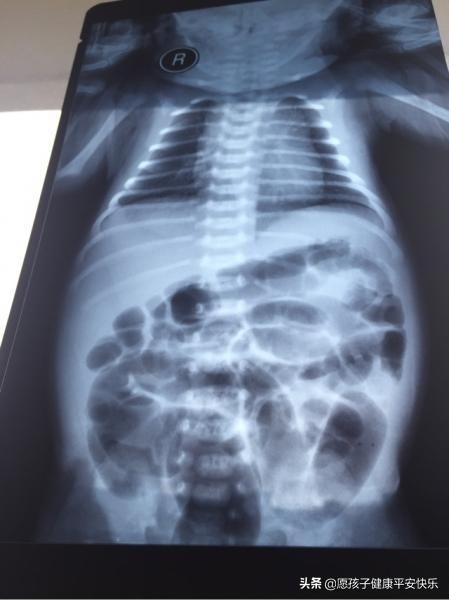

新生儿肺炎是新生儿时期常见性疾病,也是导致新生儿死亡的主要原因之一,高发期是在冬春季节,极易感染细菌,特别是早产儿,身体各方面的器官发育还不够成熟,抗病能力非常弱。

那么新生儿肺炎会有那些症状呢?

1.呼吸急促,新生儿的肺容量极小,正常新生儿呼吸频率是在40次/分左右,如果新生儿呼吸频率高达每分钟60次/分时,要引起重视了,很可能是肺叶尖端出现了感染,要及时去检查。

2.咳嗽不停,根据新生儿的咳嗽情况进行判断即可,如果新生儿只是短暂的咳嗽,过后并无异常,那就是正常的,如果咳嗽连续不断,丝毫没有减退迹象,并伴随着发热症状,那可能就是患上肺炎了。

3.口吐白沫,这是判断新生儿肺炎症状的重要标识,白沫是气管内的分泌物,需要注意的是宝宝吐出来的不是白色口水泡泡哦,是白沫,家长一点要学会辨别哦。

4.面部发紫,当新生儿患上肺炎后会因缺氧而导致呼吸困难急促出现面目发紫,嘴唇发白,四肢冰凉的情况。